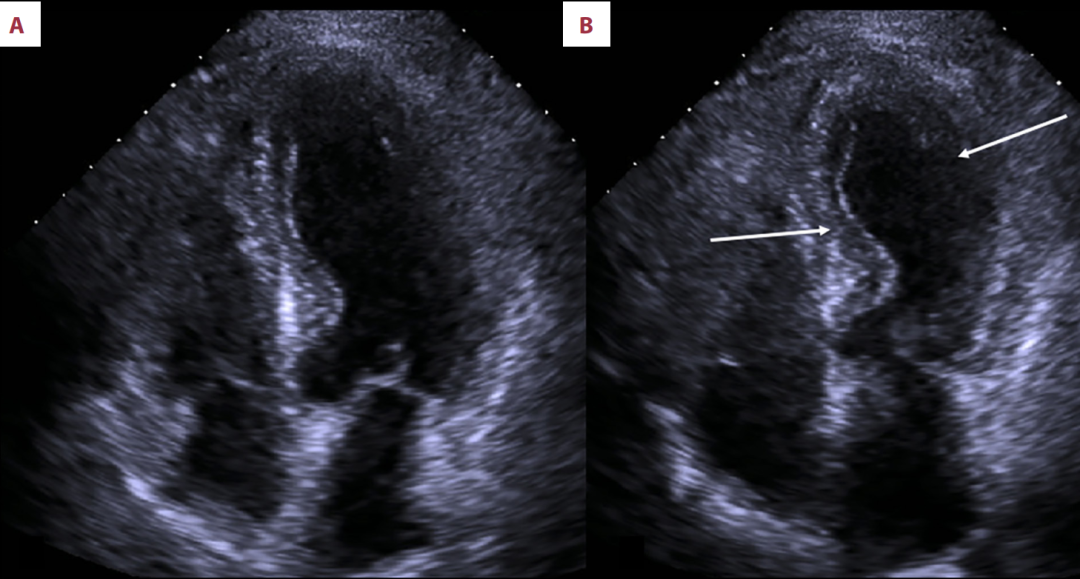

第一次(2013年)发作(图3):表现为中远段前间隔和中侧壁的运动减弱,LVEF更低(40%),并伴有I型舒张功能障碍。

图3

2013年经胸超声心动图显示的心脏四腔图像;舒张期(A)与收缩期(B)。箭头标出了收缩期时心室下壁及中段前外侧壁的运动缺失情况。